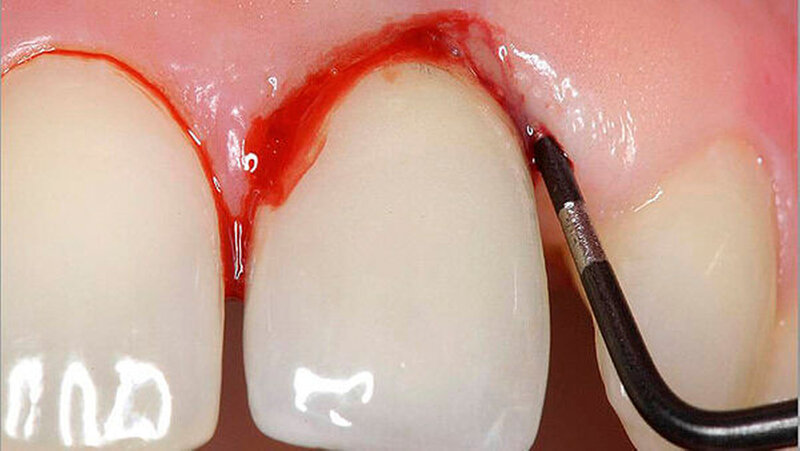

Es ist bekannt, dass Patienten mit Diabetes mellitus häufiger und schwerer von Parodontitis betroffen sind [Bascones-Martinez et al. 2014]. Lange Zeit galt die Erkrankung als eine relative Kontraindikation für die dentale Implantologie, da auch hier von Störungen der Wundheilung und knöchernen Integration ausgegangen wurde. Auch eine erhöhte Rate an Periimplantitis und Implantatversagen wurde postuliert.

• Diabetes mellitus scheint in den ersten Jahren kein erhöhtes Risiko für periimplantäre Entzündungen darzustellen. Im Gegensatz dazu scheint das Risiko für periimplantäre Entzündung mit steigender Dauer nach der Implantation anzusteigen.

• Da Patienten mit Diabetes mellitus ein höheres Risiko für Periimplantitis aufweisen, sollte eine risikoadaptierte Nachsorge nach Implantatinsertion erfolgen.